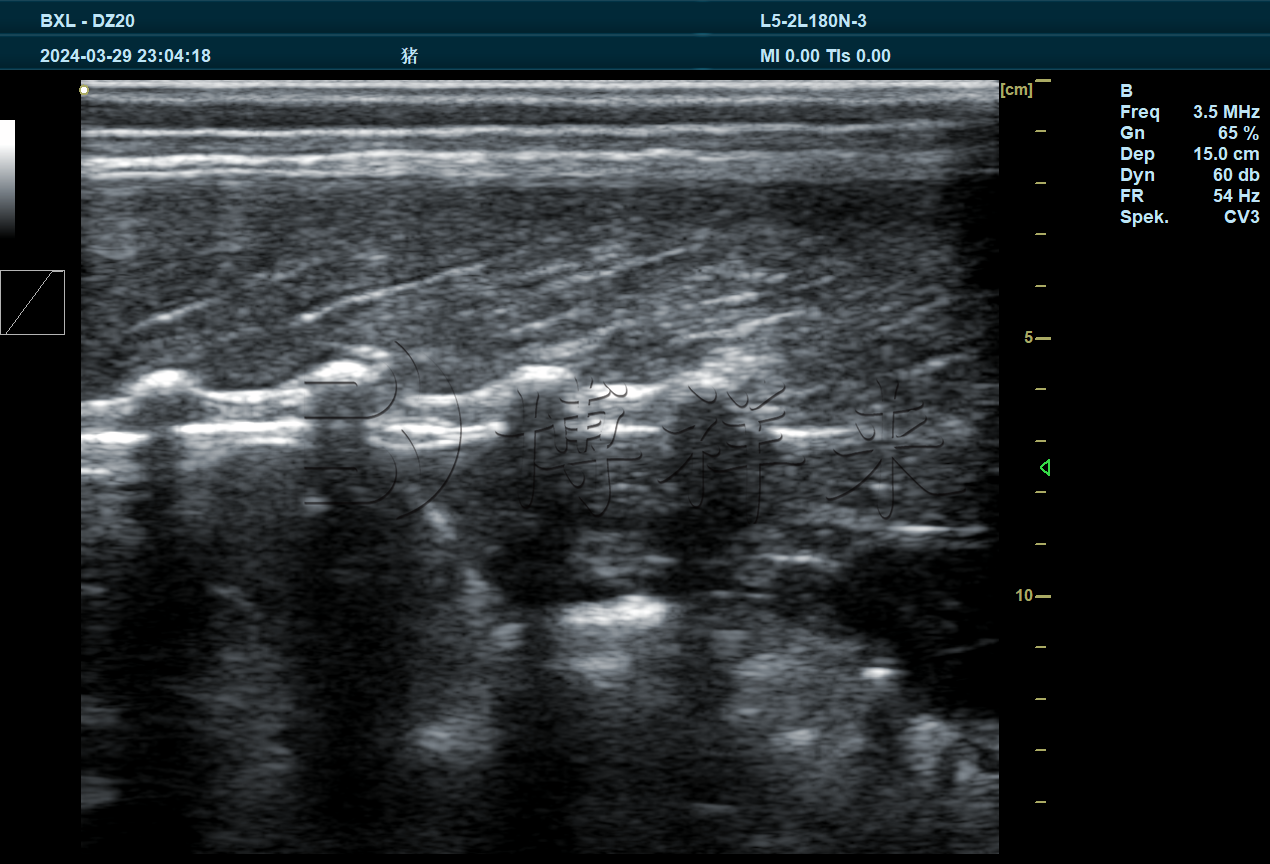

猪背标纵切超声图

• 背膘厚度的精准测定:通过在标准位置(第3~4肋之间)获取脂肪层图像,自动或手动标注脂肪厚度,为评估猪只瘦肉率及育种价值提供量化依据。